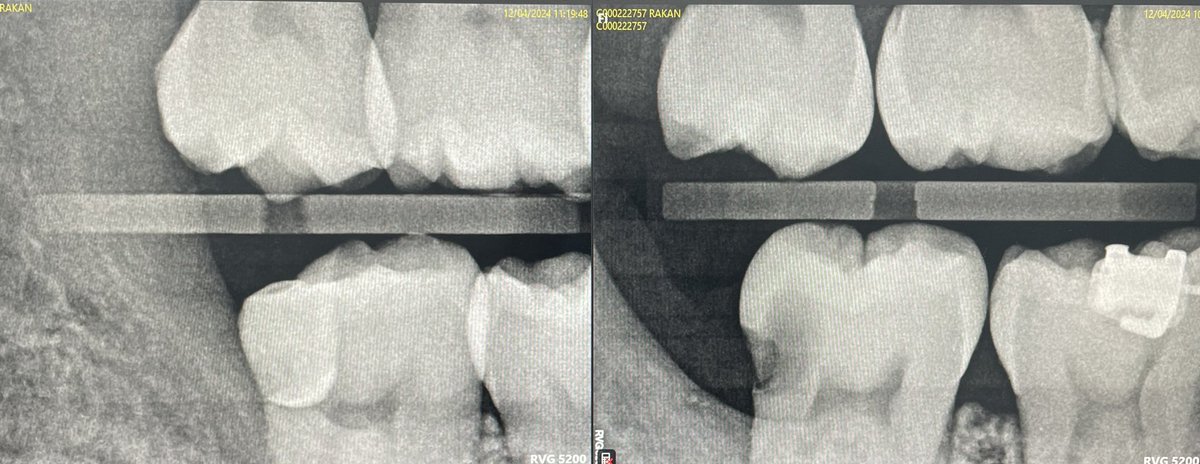

Case of the day #47 OD caries diagnoses Pulp: reversible pulpitis

Periapcal : Normal

VPT approach by direct pulp caping with MTA.

Pt will follow up after 2 weeks for assessment